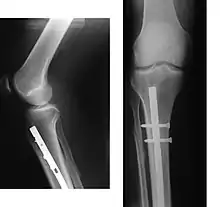

Since bone healing is a natural process that will occur most often, fracture treatment aims to ensure the best possible function of the injured part after healing. Bone fractures typically are treated by restoring the fractured pieces of bone to their natural positions (if necessary), and maintaining those positions while the bone heals. Often, aligning the bone, called reduction, in a good position and verifying the improved alignment with an X-ray is all that is needed. This process is extremely painful without anaesthesia, about as painful as breaking the bone itself. To this end, a fractured limb usually is immobilized with a plaster or fibreglass cast or splint that holds the bones in position and immobilizes the joints above and below the fracture. When the initial post-fracture oedema or swelling goes down, the fracture may be placed in a removable brace or orthosis. If being treated with surgery, surgical nails, screws, plates, and wires are used to hold the fractured bone together more directly. Alternatively, fractured bones may be treated by the Ilizarov method which is a form of an external fixator.

Surgery

Surgical methods of treating fractures have their own risks and benefits, but usually, surgery is performed only if conservative treatment has failed, is very likely to fail, or is likely to result in a poor functional outcome.[39] With some fractures such as hip fractures (usually caused by osteoporosis), surgery is offered routinely because non-operative treatment results in prolonged immobilisation, which commonly results in complications including chest infections, pressure sores, deconditioning, deep vein thrombosis (DVT), and pulmonary embolism, which are more dangerous than surgery.[40] When a joint surface is damaged by a fracture, surgery is also commonly recommended to make an accurate anatomical reduction and restore the smoothness of the joint.